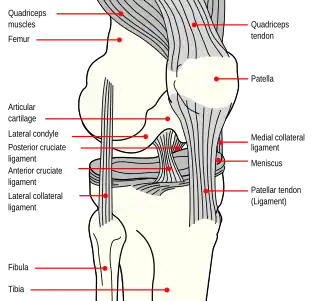

Diagram of the right knee. Anterior cruciate ligament labeled at center left. | |

The anterior cruciate ligament (ACL) is one of a pair of cruciate ligaments (the other being the posterior cruciate ligament) in the human knee. The two ligaments are called "cruciform" ligaments, as they are arranged in a crossed formation. In the quadruped stifle joint (analogous to the knee), based on its anatomical position, it is also referred to as the cranial cruciate ligament.[1] The term cruciate is Latin for cross. This name is fitting because the ACL crosses the posterior cruciate ligament to form an "X". It is composed of strong, fibrous material and assists in controlling excessive motion by limiting mobility of the joint. The anterior cruciate ligament is one of the four main ligaments of the knee, providing 85% of the restraining force to anterior tibial displacement at 30 and 90° of knee flexion.[2] The ACL is the most frequently injured ligament in the knee.

Structure

The ACL originates from deep within the notch of the distal femur. Its proximal fibers fan out along the medial wall of the lateral femoral condyle.[3] The two bundles of the ACL are the anteromedial and the posterolateral, named according to where the bundles insert into the tibial plateau.[4][5] The tibial plateau is a critical weight-bearing region on the upper extremity of the tibia. The ACL attaches in front of the intercondyloid eminence of the tibia, where it blends with the anterior horn of the medial meniscus.